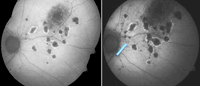

12. De los 18 pacientes de su serie, en 11 realizan retinografías y AFF seriadas a lo largo de una media de 18 meses. Estos autores observan que el desarrollo de nuevas lesiones visibles en la funduscopia se produce en áreas donde en exploraciones previas se observaban alteraciones sólo en la AFF. Es decir, los hallazgos en la AFF precedían a los hallazgos funduscópicos. Dichas alteraciones consistían en

spots hipoautofluorescentes de menos de 125 µm. Este hallazgo es de gran utilidad en términos de valoración de la actividad inflamatoria en la CMP. La

Figura 1 muestra imágenes de una paciente seguida en nuestra unidad.

Figura 1. Paciente afecta de coroiditis multifocal con panuveítis. La flecha muestra el desarrollo de lesiones aun estando asintomática.